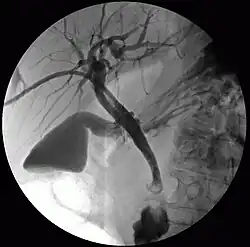

![]() Percutaneous transhepatic cholangiography | |

Cholangiography is the imaging of the bile duct (also known as the biliary tree) by x-rays and an injection of contrast medium.[1]

- Percutaneous transhepatic cholangiography (PTC): Examination of liver and bile ducts by x-rays. This is accomplished by the insertion of a thin needle into the liver carrying a contrast medium to help to see blockage in liver and bile ducts.